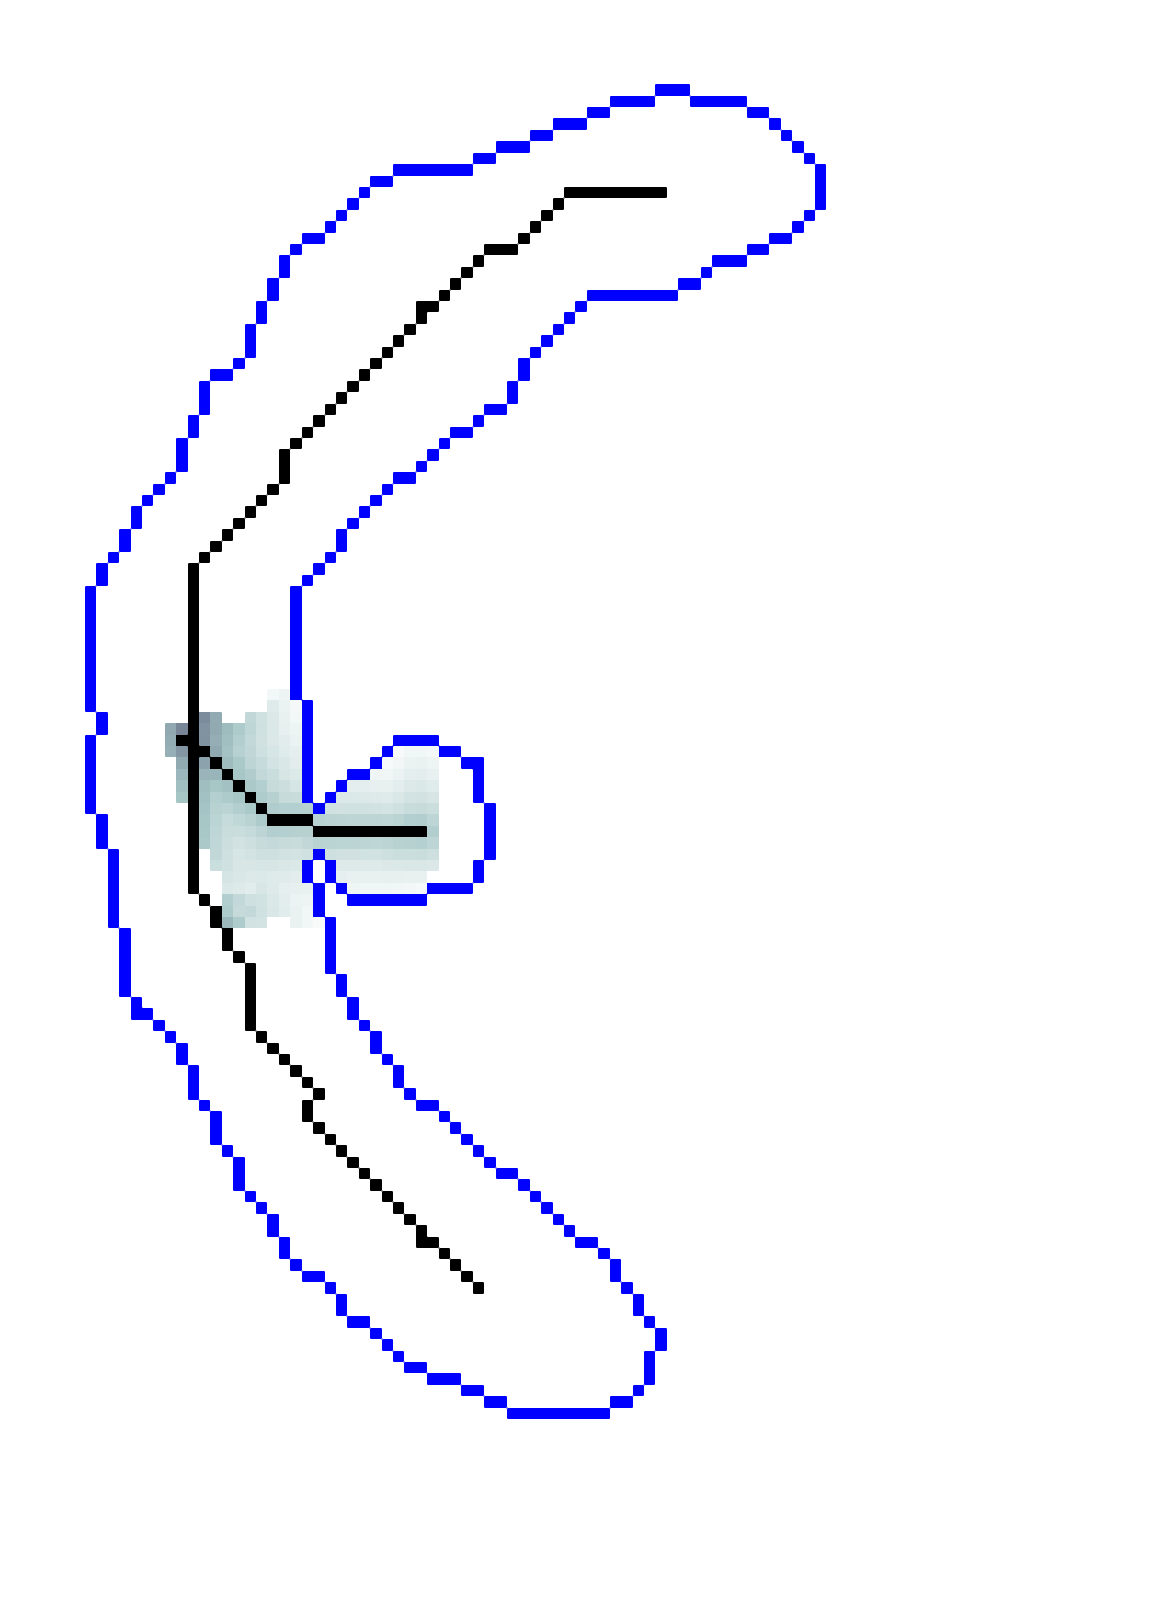

Geodesic paths are determined by back-tracing when different regions collide. The connecting geodesic is extracted minimizing at the collision grid-points. The aFM maps, i.e. ; the Voronoi index map , representing the label associated to each propagating seed; and the Tag , representing the state of each grid-point (Front, Visited, Far), are then updated within the collided regions, so that these merge as one and the front is consistent with the unified resulting region. This is continued until all regions merge.

Initialization. The seeds are aligned towards the vessels’ mid-line with a constrained gradient descent, resulting in an initial set of sources . All 26-connected components initialize the aFM maps, i.e., , , , and constitute also the initial geodesics .

Fast Marching Step. The aFM maps are updated by following an informative propagation scheme. We refer to [4] for the 3D aFM step considering the 48 simplexes in the 26-neighbourhood of the Front grid-point with minimal .

Path Extraction. Collision is detected when Visited grid-points of different regions are adjacent. A connecting is determined by linking the back-traced minimal paths from the collision grid-points to their respective sources with a gradient descent on (fig. 2). The associated integral geodesic length is computed and the connectivity in is updated in the form of an adjacency list. Lastly, the grid-points of the extracted are further considered as path seeds in the updating scheme, since furcations can occur at any level of the connecting minimal paths.

Fast Updating Scheme. A nested aFM is run only in the union of the collided regions using a temporary independent layer of aFM maps, where , , and . Ideally, the nested aFM is run until complete domain exploration, however, to speed up the process, the propagation domain is divided into the solved and unsolved sub-regions, and the update is focused on the latter (fig. 2). The boundary geodesic values of equal the geodesic distances at the collision grid-points. Lastly, the aFM maps are updated as: , , and .

| Initialization | FM Steps | Collision, Path Extraction and Update | Convergence | ||||||

| Descent | … | Stop Criterion | |||||||